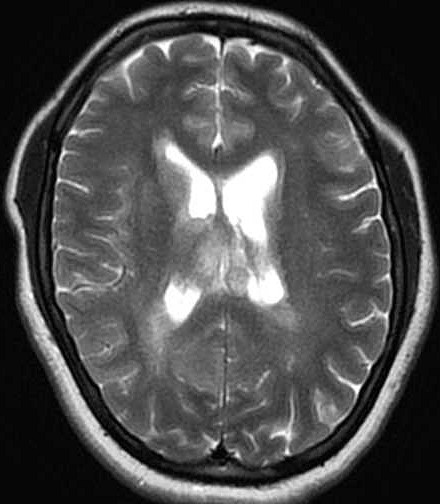

| Fem. 17a. |

| Nódulo sólido homogêneo preenchendo o III ventrículo, com limites precisos, com hipossinal em T1 e hipersinal em T2 e FLAIR, que se impregna por contraste paramagnético. Lesão menor implantada no assoalho do IV ventrículo provavelmente representa disseminação por via liquórica. |

| F. 17a. Tumor teratóide rabdóide atípico de III ventrículo. RM | HE | VIM, GFAP | HHF35, desmina, 1A4 | AE1AE3, EMA |